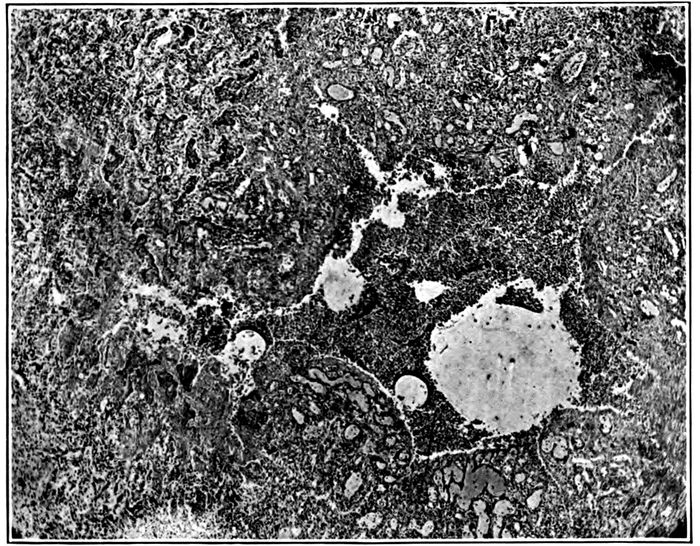

| 2214. | Endophlebitis occurring in association with suppurative pneumonia | 219 |

| 15. | Abscesses in two clusters caused by S. aureus in upper part of right upper lobe | 227 |

| 16. | Abscesses in cluster caused by S. aureus at apex of right lobe | 228 |